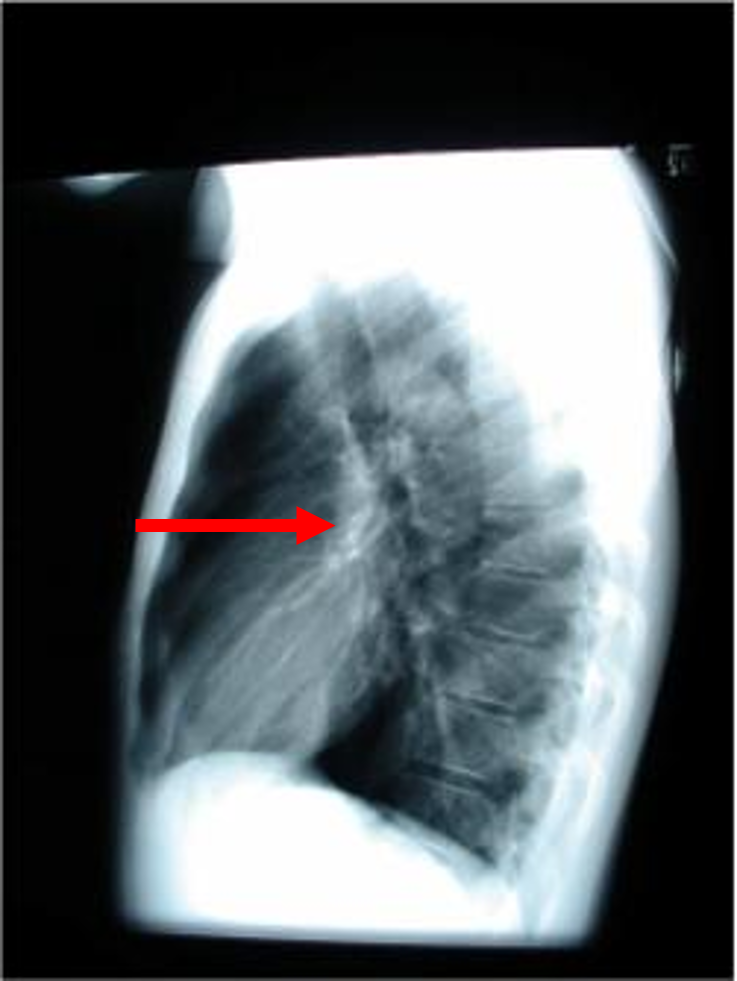

lateral chest

three rules of a lateral chest x ray

diaphragm shadow

retrosternal space

retrocardiac space